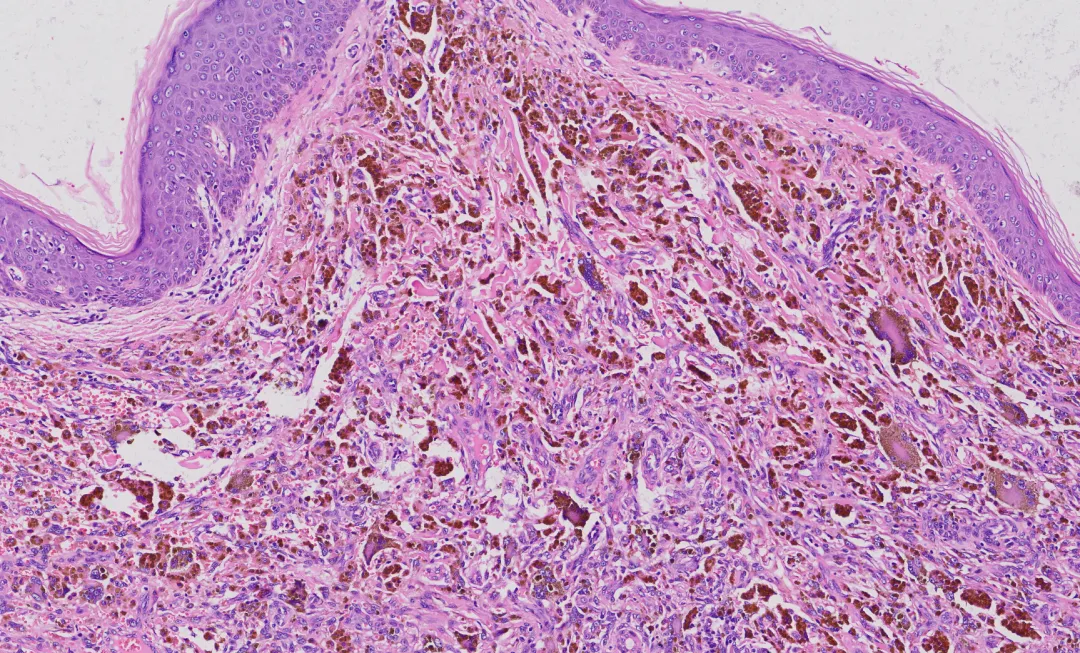

角化过度,表皮增生肥厚,皮突延长,肿瘤位于真皮内,排列较紊乱,肿瘤中央可见出血性裂隙,真皮乳头部可见无浸润带。

a.上皮样 / 梭形细胞结节:片状 / 巢状排列,胞质丰富嗜酸,核轻度异型。

b.假血管瘤样腔隙:腔隙充满血液,无内皮衬覆(关键)。

c.厚纤维假包膜:伴含铁血黄素沉积。

d.包膜外淋巴浆细胞套:可见生发中心。